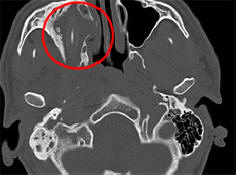

Egyes betegségek és sérülések annyira észrevétlenek, hogy egy ember évekig élhet velük gyanú nélkül létezését. Mint egy amerikai, aki majdnem két évet vett igénybe saját agyfolyadék szivárgása orrfolyás esetén, német állampolgár sikerült 15 évet élni egy ceruzával a fejében, jelentések Spiegel. Ahogy az egyetemi kórház képviselői elmondták Aachen, Észak-Rajna – Vesztfália, 24 éves afgán német származásuk 2011-ben kapott segítségüket. fiatal a személy tartós fejfájásról, megfázásról és rosszabbodásról panaszkodott látás az egyik szemben. Az orvosok sokáig nem tudták megérteni, mi történik. nem végzett számítógépes tomográfiát. Kiderült, hogy a fejemben van a beteg egész idő alatt 10 centiméteres ceruza volt. Ő az közvetlenül a fiatalember jobb szemének aljzata felett helyezkedik el, és ráhelyezhető a nyomás. Egy német, aki névtelen maradni nem tudott magyarázni honnan származott a ceruza a fejében, de később emlékezett rá milyen sikertelenül esett le gyermekkorban. Az orvosok idegen testet távolítottak el a fejről fiatal férfiak, és hamarosan felépült. Csak május végén, majdnem egy év elteltével a műtét után az orvosok úgy döntöttek, hogy erre az esetre fordítanak külön konferencia, amelynek köszönhetően az újságírók megismerkedtek róla. Nem ez az első alkalom, hogy egy ember hosszú ideig megbirkózott élj idegen tárgyal a testében. Tehát 2007-ben idős német nő, fejfájás és orrvérzés miatt, eltávolítottak egy ceruzát, amely már 50 éve ott volt.